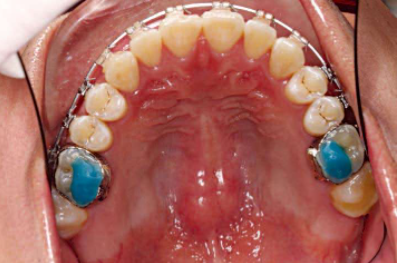

1、粘托槽的时候,如果无法明确判断牙齿的三维形态,可以把石膏模型放在旁边。最好在粘托槽之前,仔细分析石膏模型,观察牙齿的三维形态。一定要从颌面检查托槽是否在牙齿的近远中向的中心位置,可以利用口镜在口内从颌面观察托槽位置。必要时,也可以根据全景片明确牙体长轴(图1,图2)。